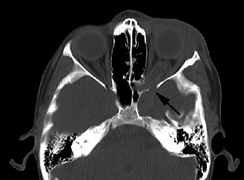

CNS hemangiomas are the most common tumor of VHL, affecting 60% to 80%, with a predilection for the cerebellum and spinal chord. An enlarging cystic component is a frequent finding in symptomatic tumors. Patients typically present in their early 30s; headaches or neck pain in affected individuals should not be ignored.172,173 On microscopy, CNS hemangiomas resemble retinal capillary hemangiomas. Their malignant potential is low.174 The treatment is surgical (Fig. 17, A and B).13

Fig. 17. Images from a 13-year-old boy with Von Hippel-Lindau syndrome. (a) Coronal postcontrast T1-weighted imaging reveals a cystic lesion with an enhancing nodule at the pial surface typical of a hemangioblastoma. (b) A second solid enhancing hemangioblastoma is seen at the craniocervial junction on a sagittal postcontrast T1-weighted image. (c) Associated cystic lesions (arrows) are seen within the pancreas.

PANCREAS.

Pancreatic lesions may be nonsecretory (most commonly cysts or cystadenomas) or secretory (islet cell tumor).179 In one study of 52 patients, 56% (29 patients) were found to have pancreatic lesions. The majority (19 of 29) had cystic changes only (Fig. 17C). Pancreatic lesions were the only abdominal manifestation of disease in 6 of 52 patients.180 In a separate study, pancreatic cysts did not show significant progression on follow-up examinations over an average period of 5 years.181 Like pancreatic cysts, islet cell tumors appear to be frequently asymptomatic.182